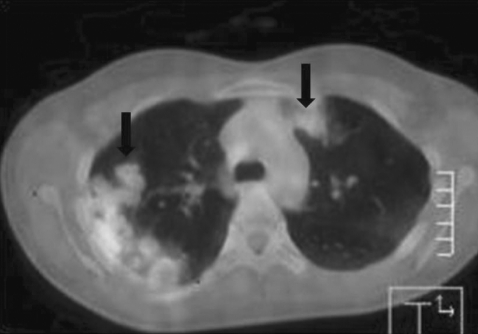

Fig. 1B). FDG-PET CT was performed to find out a possible primary site of malignancy. However, it revealed no remarkable abnormal finding except an increased FDG uptake (max SUV: 3.1) in the lung lesions (

Fig. 2). Bronchoscopic and cytological examination of the sputum showed nothing of particular significance. We could not observe parasite eggs in stool, sputum, or bronchoalvelolar lavage (BAL) fluid. However, ELISA (Genedia Ab ELISA, Green Cross MS, Yongin, Korea) was positive for antibodies against

Fig. 2FDG-PET CT showed increased FDG uptake (max SUV: 3.1) (arrows).